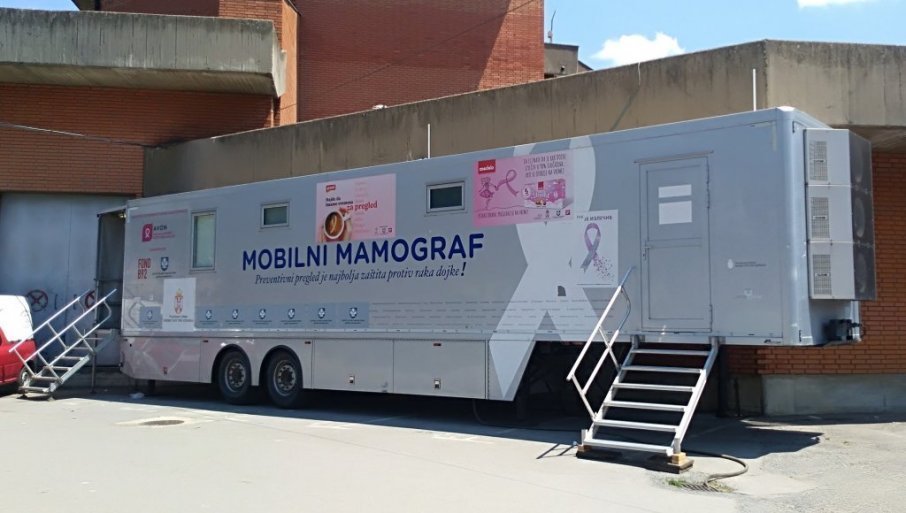

DETALJAN SPISAK: Ove preglede žene mogu obaviti besplatno širom Srbije

DRŽAVA organizuje besplatne preglede i skrining programe širom Srbije, iskoristite priliku za rano otkrivanje bolesti i očuvanje zdravlja.